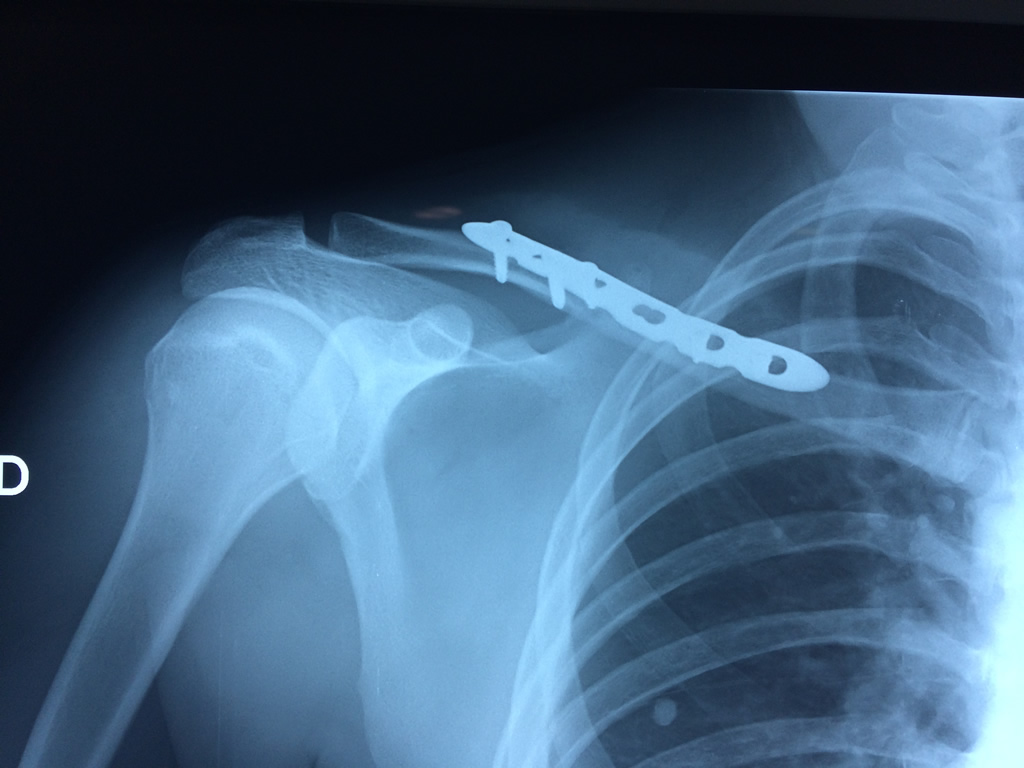

Húmero - Clavícula

La clavícula es un hueso largo, con forma de "S" itálica, situado en la parte anterosuperior del tórax. Junto con la escápula forman la cintura escapular. Se puede palpar por toda su longitud y se extiende del esternón al acromion de la escápula, siguiendo una dirección oblicua lateral y posterior.

Se considera el único medio de unión entre el miembro superior y el tórax. A pesar de su aspecto, similar al de un hueso largo, posee una estructura semejante a la de un hueso plano, ya que carece de epífisis y de diáfisis, lo que la harían entrar dentro de la clasificación de hueso largo. Carece de un canal medular propiamente dicho.